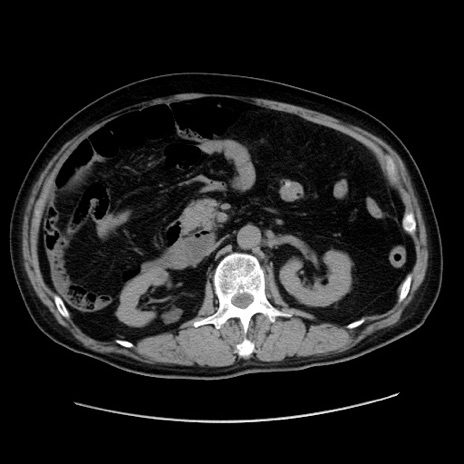

症例30(横断像)

【症例】80歳代男性

【主訴】臍周囲痛

【現病歴】約6時間前から臍下部痛が出現。次第に腹部膨隆・背部痛も生じてきたため来院。背部痛の場所は変化しない。

【身体所見】意識清明、BT 36.3℃、BP  131/87mmHg、P 87bpm、SpO2 100%(RA)、臍周囲自発痛・圧痛あり、反跳痛なし、自発痛部位に一致して板状硬あり、腹部膨隆、腸雑音減弱、CVA tenderness両側陰性。

【データ】WBC 19600、CRP 0.33